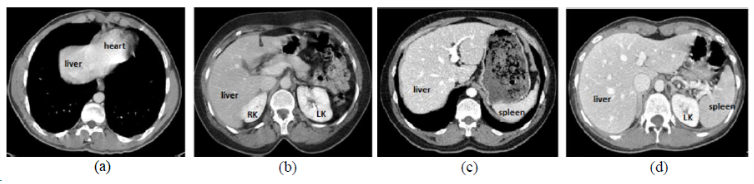

肝脏

LiTS数据集包含131套训练扫描和70组测试数据,其中70组测试数据标签不公开。LiTS训练集中包含3DIRCADB中的所有数据,所以如果合并多个数据集不要合并这两个。Medical Segmentation Decathlon中肝脏分割的数据集就是LiTS。

CHAOS

| CHAOS | 肝/肾/脾 | 分割 | CT+MRI | 40CT+120MRI | 0/1标签 | dcm | CC 4.0 |

CHAOS是一个多脏器,多模态分割数据集。